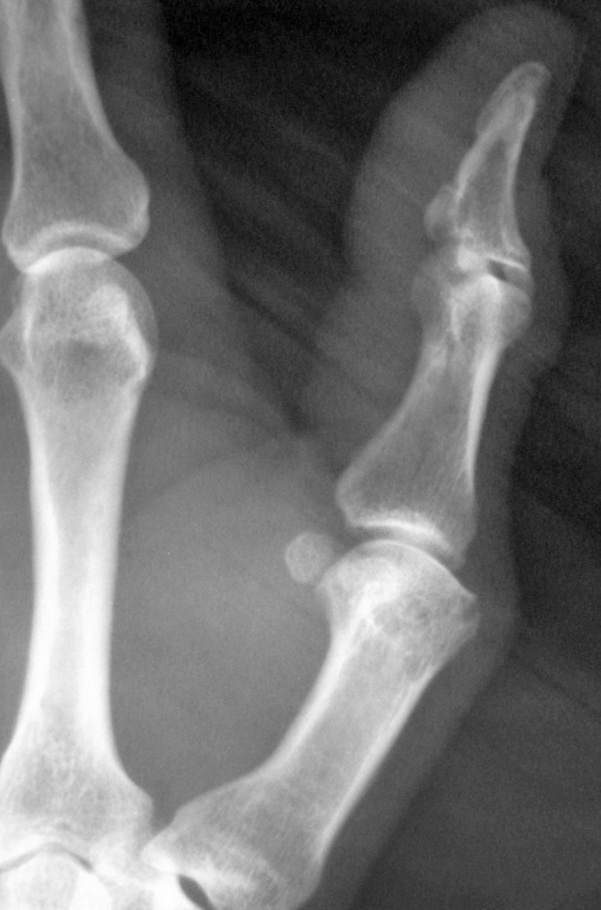

男,60,拇指掌指及指间关节疼痛15天。第一掌骨头低密度及箭头所指骨样突起正常吗

第一掌骨头局部低密度,考虑退变吧

手部经常可见囊状低密度区,可能为纤维性改变,无临床意义

箭头所指考虑纤维性骨皮质缺损。没有临床意义